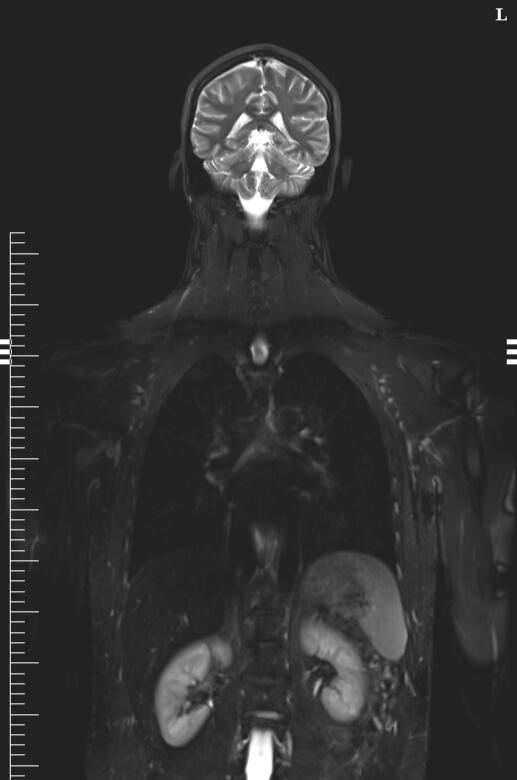

OneMRI provides patients with access to whole-body MRI services in convenient locations around Australia. Previously only available to a select few, OneMRI's mission is to make whole-body MRI more accessible to the general public for the early detection of cancer and chronic disease.